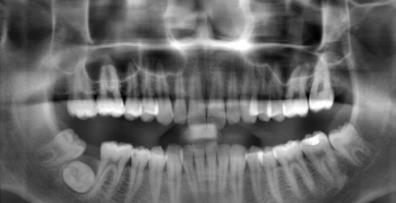

張拍片圖片如下:

從(cong) 拍片結果可以看出,7號牙齒是隱藏在牙槽骨內(nei) 的,但是通常肉眼直觀是看不到的,因為(wei) 牙冠偏裏側(ce) ,牙根偏外側(ce) 阻生,根本沒長出來的!這種情況不拍片怎麽(me) 知道7號牙的情況,如果不了解清楚,就製定矯治方案,豈不是胡來嗎?